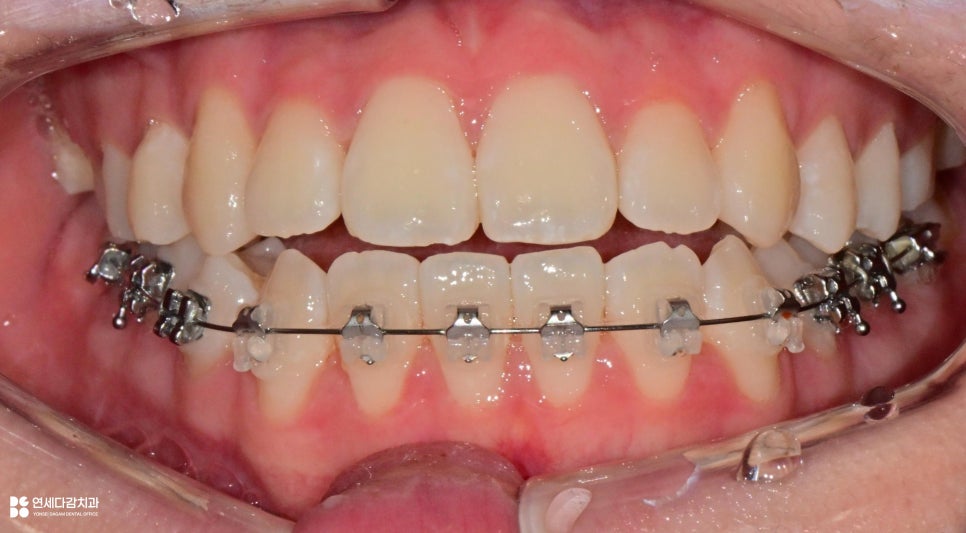

가락동 치과 에서 보여드리는 것과 같이

매복된 사랑니가 뒤쪽 공간을 차지하면

이동 자체에 제약을 줄 수 있기 때문에

발치가 필수인 경우가 있습니다.

특히 미성숙한 사랑니의 경우

대부분이 잇몸 속에 매복되어 있고

2026.01.06

사진처럼 육안으로는 확인되지 않지만,

비정상적으로 자리 잡을 때가 많습니다.